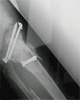

Post

Op

Xrays : alignment maintained with restoration of joint height